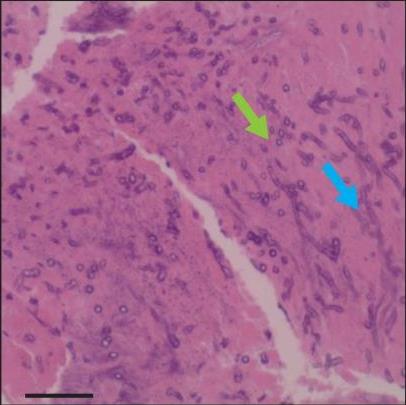

• 侵袭性肺真菌病的支气管镜表现及介入治疗效果

2025, 31(9):81-90. DOI: 10.12235/E20250317

摘要 (112) HTML (56) PDF 6.06 M (77) 评论 (0) 收藏

摘要:目的 探讨侵袭性肺真菌病(IPFD)的支气管镜表现,并评估介入治疗的安全性和疗效。方法 回顾性分析2018年5月12日-2025年5月12日于该院行支气管镜检查的35例IPFD患者的临床资料,观察IPFD的支气管镜表现及介入治疗效果。结果 共收集35例患者临床资料。其中,男22例,女13例,患者年龄(53±14)岁。基础疾病包括:血液系统恶性肿瘤10例,长期应用糖皮质激素者5例,2型糖尿病者4例,肺部恶性肿瘤2例,器官移植1例。胸部CT显示:肺部病变累及单肺叶者19例,累及多肺叶者16例。支气管镜下表现主要为:黏膜充血水肿29例(82.9%)、坏死物堵塞管腔22例(62.9%)、大量黏稠脓性分泌物17例(48.6%)、支气管部分狭窄或闭塞16例(45.7%)、黏膜坏死9例(25.7%)、黏膜出血5例(14.3%)、真菌球3例(8.6%)。其中,32例(91.4%)接受全身性抗真菌治疗,17例(48.6%)接受支气管镜局部两性霉素B灌注治疗,10例(28.6%)采用活检钳钳除病灶,6例(17.1%)采用冷冻探头冻取病灶,4例(11.4%)接受氩气刀治疗。28例(80.0%)临床症状明显改善,肺部影像学病灶缩小或消退;4例(11.4%)病灶稳定;3例(8.6%)未完成治疗。结论 IPFD多见于免疫抑制宿主,支气管镜常表现为:坏死物堵塞管腔、伴脓性分泌物、支气管管腔狭窄和局部黏膜充血水肿或坏死。全身抗真菌药物联合支气管镜下介入治疗,安全性高,且疗效好。